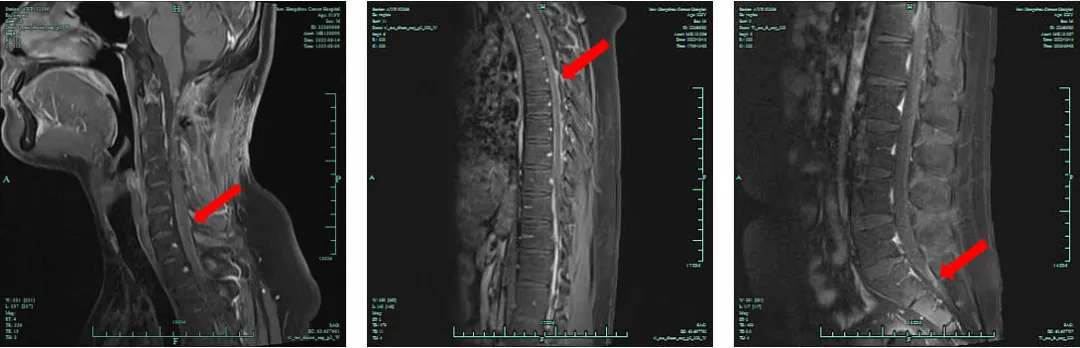

图2.放疗前脊髓MRI检查结果(2022.7.22)

(一)替莫唑胺化疗同步放疗:2022年7月11日至2022年7月22日2022年7月11日起行口服替莫唑胺280mg化疗,每日一次(QD)。7月20日、7月22日,分别行放疗前头颅、脊髓MRI检查,结果示:疾病进展(PD),颈椎、胸椎、腰椎、骶椎相应脊膜继发恶性肿瘤。

2022年8月23日,复查脊髓MRI,疗效评价为部分缓解(PR);双下肢肌力5级。

图3.放疗末期复查脊髓MRI检查结果(2022.8.23)